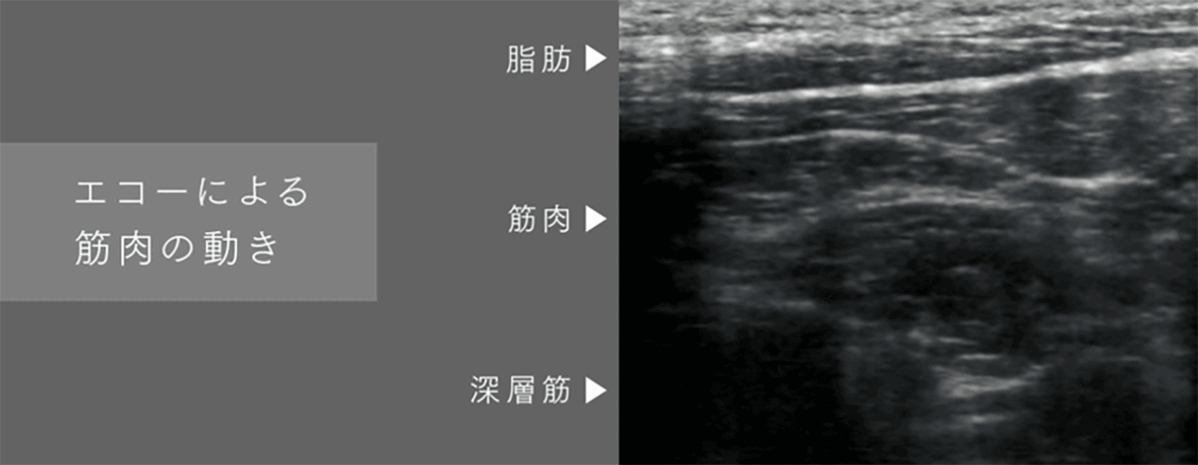

EMS機能は「たたき・もみ・つまみ」を再現した3種類のEMSモードと20段階のレベル調整が可能。

※1*電気刺激による筋肉運動によって固まった筋肉を動かす